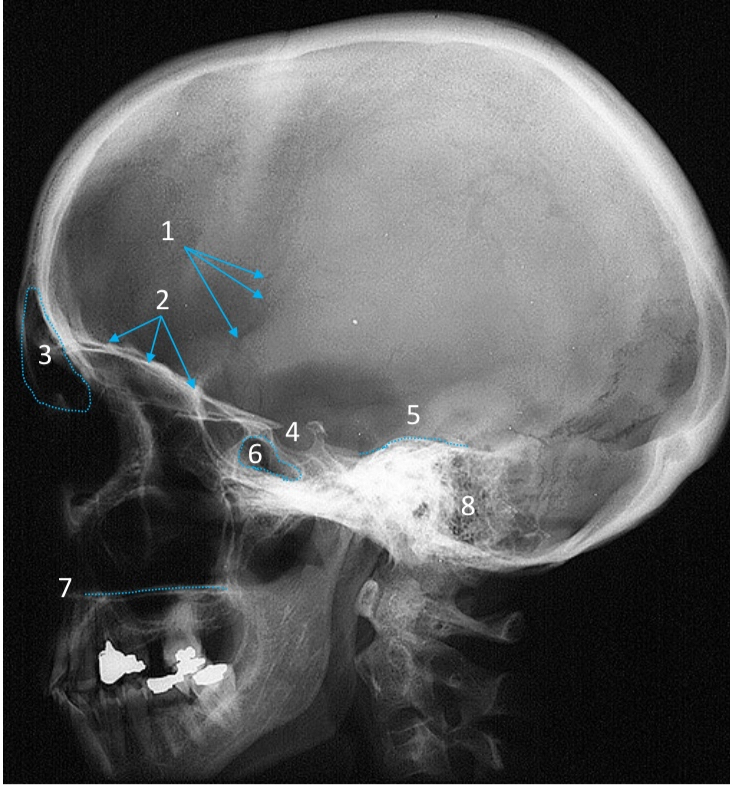

Mandible

ID bone

Maxilla

ID bone

Frontal sinus

ID structure

Pituitary fossa

ID structure

Occipital

ID bone

Lambdoid suture

ID structure

Frontal sinus

ID structure

Orbital margin

Orbit

Maxillary sinus

ID structure

Mandibular condyle

ID structure

Inferior nasal concha

ID structure

Hard palate

ID strucutre

Gonial angle

ID strucutre

Petrous ridge

ID structure

Groove of middle meningeal a.

ID structure

Roof of orbit

ID structure

Frontal sinus

ID structure

Pituitary fossa

ID structure

Petrous ridge

ID structure

Sphenoid sinus

ID structure

Hard palate

ID structure

Mastoid air cells

ID structure

Zygomatic arch

ID structure

Mandibular condyle

ID structure

External auditory meatus

ID structure

Mastoid air cells

ID structure

Foramen magnum

ID structure

Foramen ovale

ID structure

Foramen spinosum

ID structure